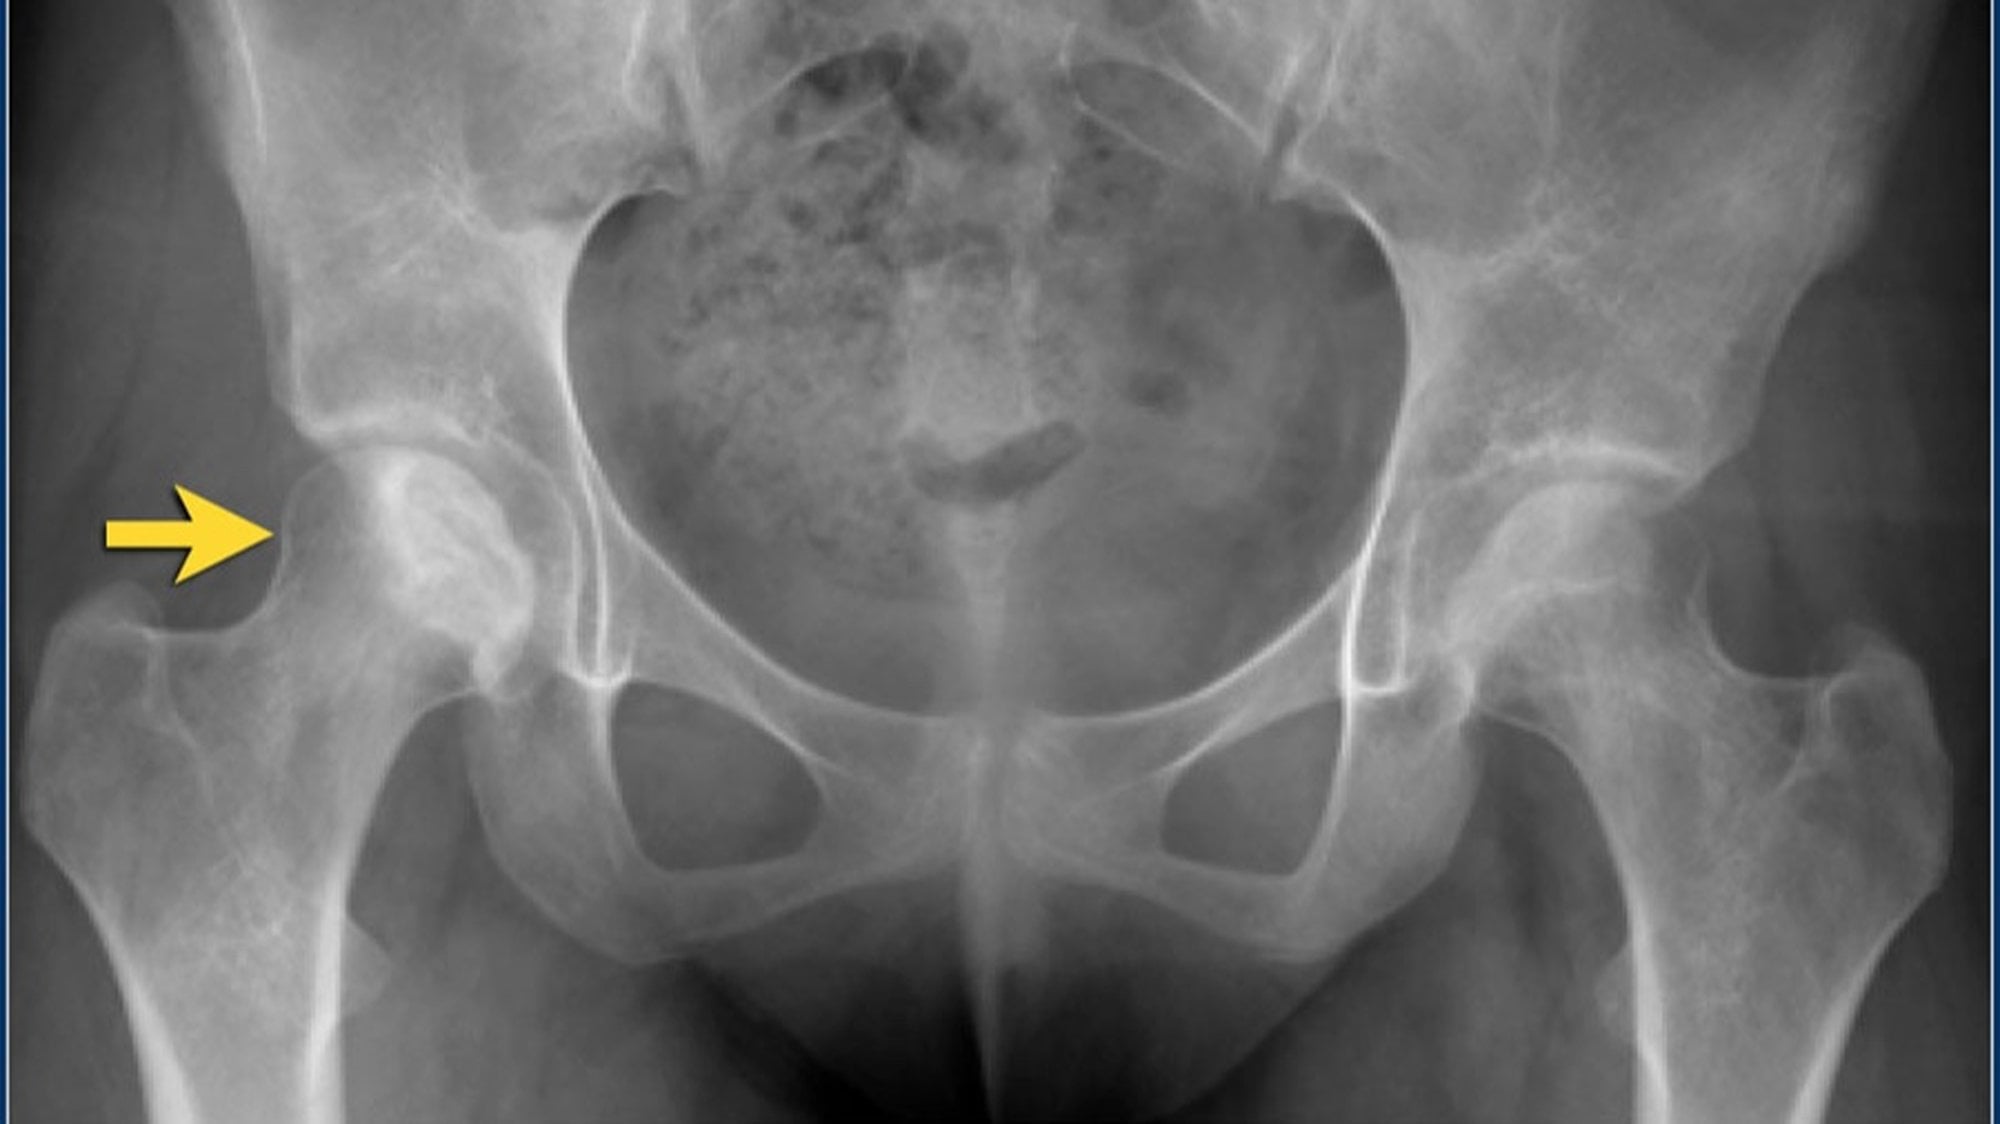

Radyografi

Avasküler Nekroz'un erken evrelerinde düz radyografik bulgular dikkat çekici değildir. Bununla birlikte, Amerikan Radyoloji Koleji, kalça ağrısı ile başvuran Avasküler Nekroz riski taşıyan hastalarda pelvis röntgenini en uygun başlangıç görüntüleme çalışması olarak görmektedir. Bu projeksiyonlardan sadece birinde eklem çökmesi veya kortikal çöküntü görülebileceğinden, hem pelvisin ön-arka görünümü hem de kalçanın kurbağa bacağı lateral görünümü gereklidir.

Hafif-orta Avasküler Nekroz'da radyografiler skleroz ve kemik yoğunluğundaki değişiklikleri gösterir. İlerlemiş hastalıkta düzleşme, subkondral radyolüsent çizgiler (hilal işareti) ve femur başının çökmesi gibi kemik deformiteleri belirgindir.

- Aşama 3:

- Hasta semptomatiktir,

- Radyografik bulgular subkondral lusensi (hilal işareti) ve subkondral çökmeyi içerir,

- Femur başının şekli genellikle radyografilerde ve BT taramalarında korunur.